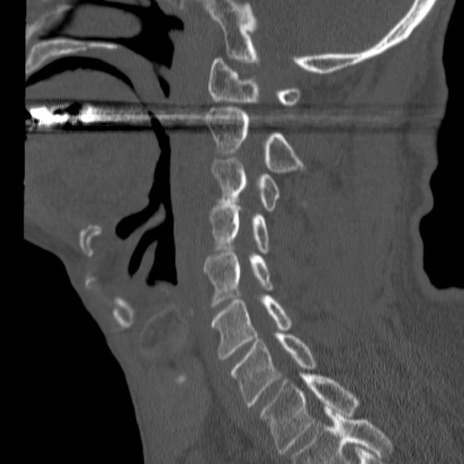

症例46 頚椎CT(矢状断像)

【症例】80歳代男性

【主訴】両側頚部〜上肢のしびれ

【現病歴】昨日、自宅内で転倒、その後より上記症状あり。意識障害なし。

【身体所見】両側上肢のallodynia(熱痛覚過敏)あり。MMTおよびDTRは正確な所見取れず。両上肢の挙上はなんとか可能。

異常所見と診断は?